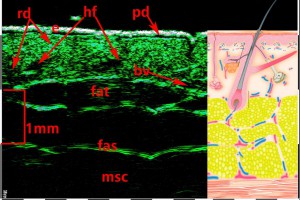

-Υπέρηχος Υψηλής Συχνότητας (HFUS) και Ιστολογία